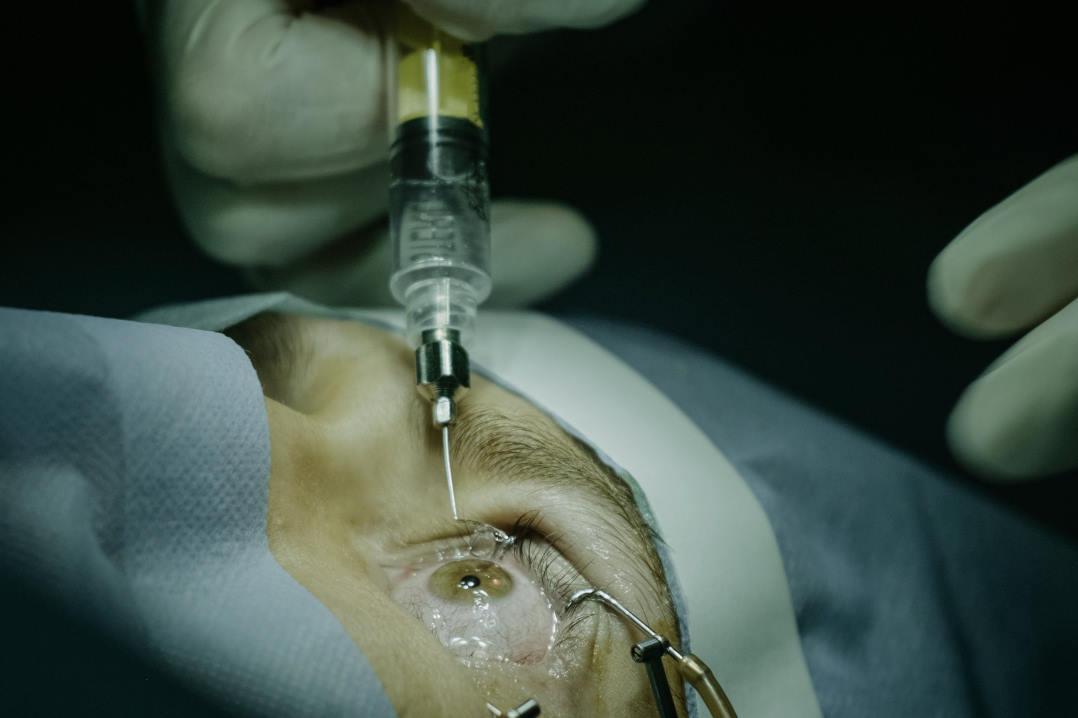

Histopathologically, both present with rod-shaped or trapezoidal hyaline deposits beneath the epithelium, with GCD2 additionally demonstrating amyloid, which is related to the lattice lesions (Fig 2).

Fig 2a. GCD2 showing discrete granular opacities (arrowheads) in the corneal stroma centrally.

Fig 2b. Manifestation of GCD2 in the corneal interface postLASIK surgery, the eye only exhibited a few small grey lesions prior to surgery.